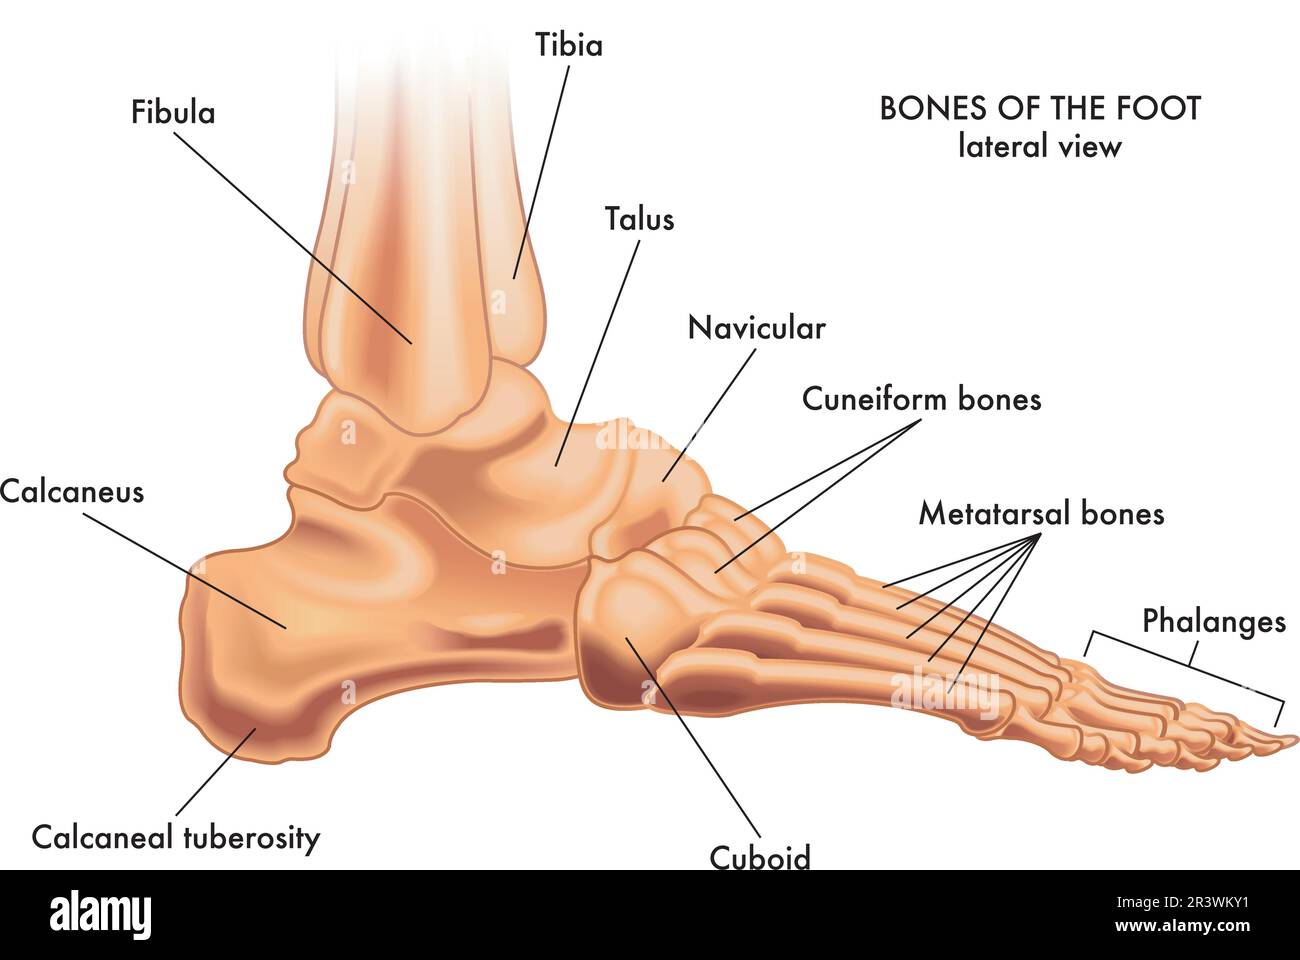

RF2R3WKY1–Illustration médicale des principales parties des os du pied en vue latérale, avec annotations.

RFTCW7F1–Os du pied et de la cheville d'illustration vectorielle médical isolé sur fond blanc eps 10 Infographie